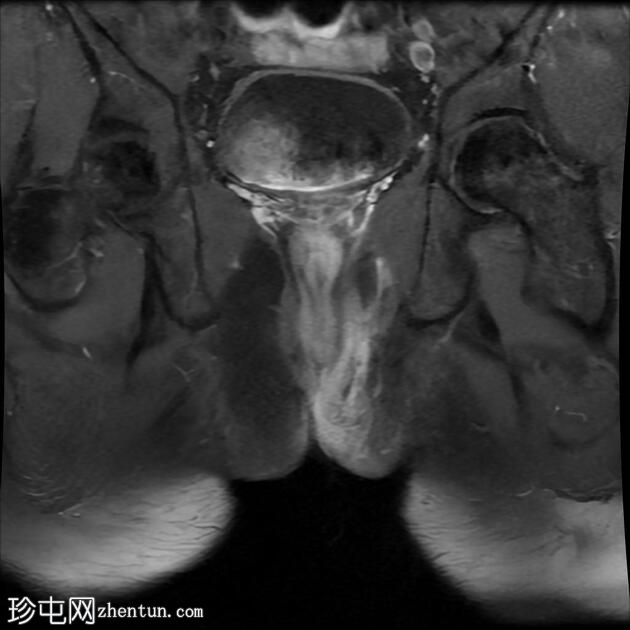

冠状位T1

脂肪饱和度

冠状位

T2

冠状位T2

一条68毫米厚的强化通道始于左侧肛周区域,向上穿过肛门内外括约肌,在2点钟方向开口于肛管。

无脓肿形成。

MRI成像特征与所述左侧经括约肌肛周瘘相符。